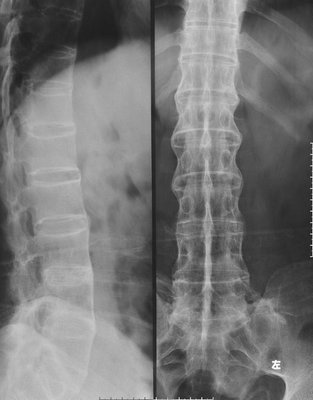

(图:X线片显示王女士相邻椎体连接成竹节样)

检查结果:CT检查结果:骶髂关节炎出现明显的软骨下骨质侵蚀、破坏,增生硬化,关节边缘呈毛刷状、锯齿状,关节间隙明显异常,韧带关节骨质破坏;脊柱X线检查结果:椎间盘间隙钙化、骨化、相邻的椎体连接成竹节样;辅助检查:轻度贫血。